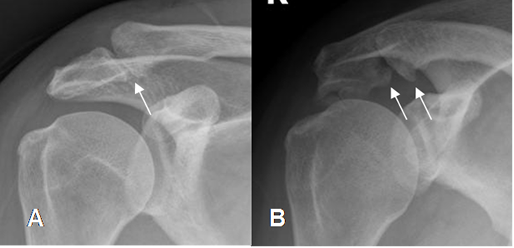

Fig 82. Cambios degenerativos en articulación acromioclavicular.

A: Rx AP y B: Rx AP con angulación caudal a 30·. Presencia de osteofitos en la parte inferior de la articulación acromioclavicular, que producen sindrome de pinzamiento.